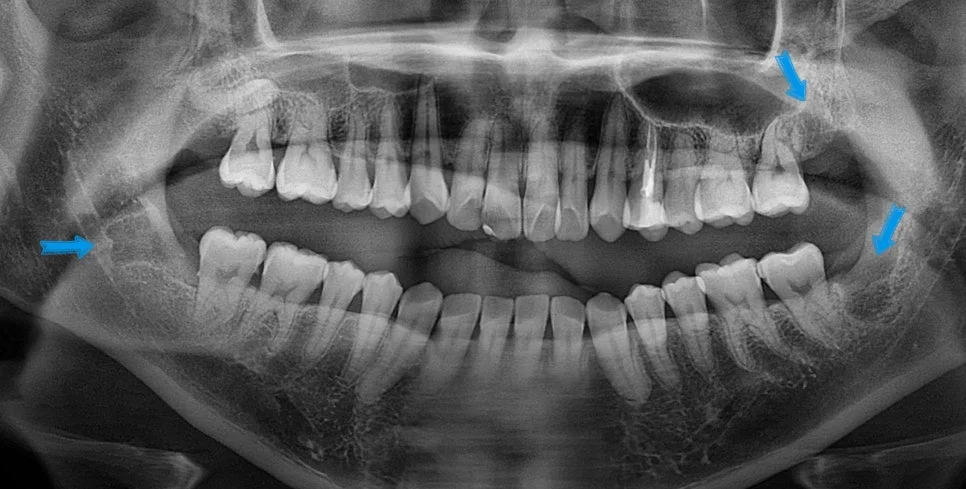

매복 사랑니 양쪽 파노라마 진단

양쪽 하악 매복 사랑니 파노라마 진단

제2대구치를 위협하는 우측 하악 매복 사랑니입니다. 잇몸 아래에 완전히 매복되어 있는 상태를 확인할 수 있습니다.

제2대구치와 사이 관리가 어려운 좌측 하악 매복 사랑니입니다. 살짝 맹출된 상태이지만 관리가 되지 않아 발치가 필요한 상태입니다.

이번 사례의 환자분은 나이가 어리셔서 사랑니 맹출이 덜 되었지만, 미리 예방 차원에서 발치를 해줘야 합니다. 왜일까요?